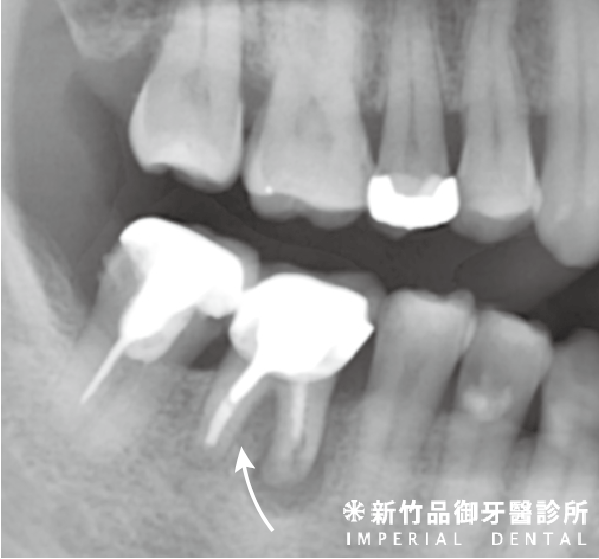

五、垂直牙根斷裂 (Vertical root fracture)

品御牙醫診所 徐孟弘醫師提供

敘述:牙根的垂直斷裂,有些會延伸到牙冠部分。

症狀:咬痛、悶痛,牙髓會逐漸壞死,根尖周圍炎可能產生膿包。

處置:大部分的情況下需要拔牙處置。部分牙齒可以由根管專科醫師做根尖切除手術保留牙齒,需要專科醫師當下判斷。